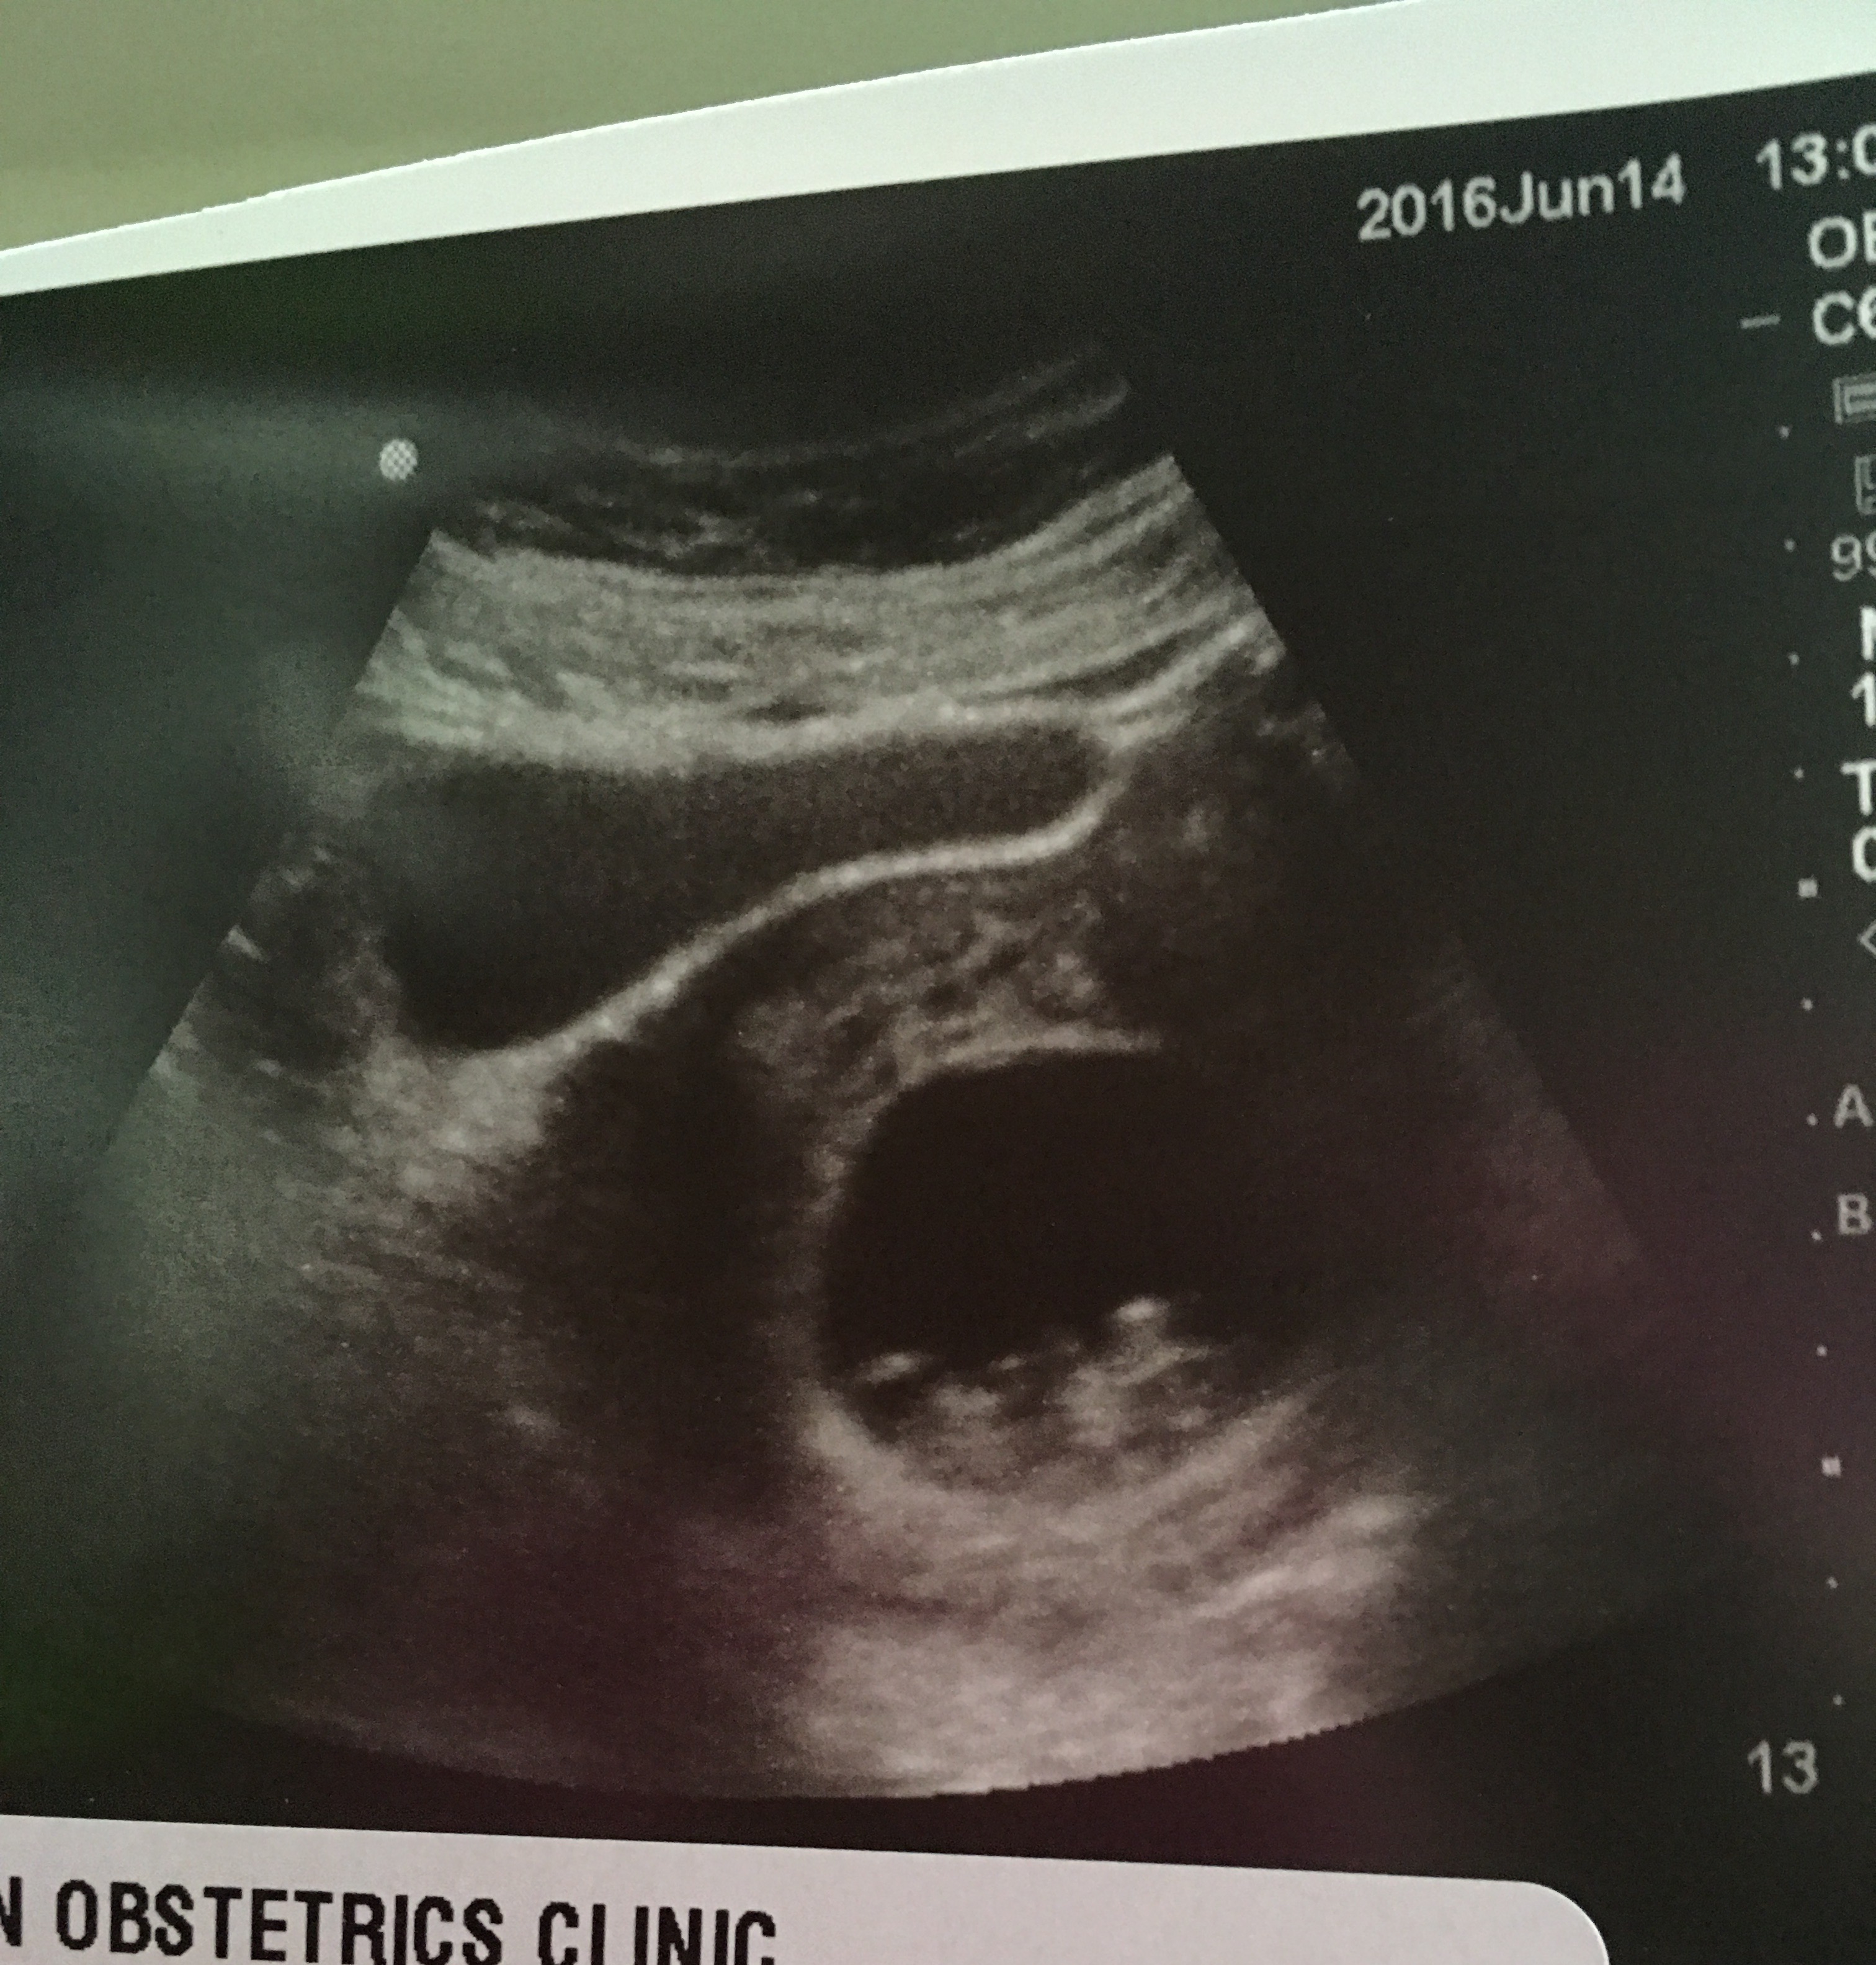

Every ultrasound scan has white spots and black spots. Infections, blood vessel disorders, inflammation, both benign & malignant tumours appear as spots on the liver. Abdominal ultrasound may be used to examine enlarged lymph nodes, especially in the abdomen.

The bone to be studied well to rule out structural defects during. The dark spots in the liver are cysts. Raju a.t (46 minutes later) brief answer: